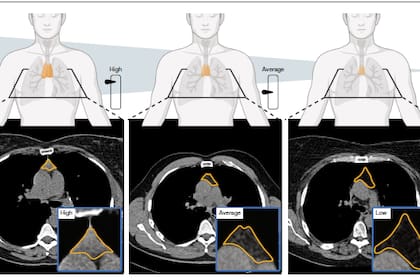

El estudio, publicado en Nature, desarrolló un sistema de aprendizaje profundo para estimar la “salud tímica” a partir de tomografías. Después aplicó ese indicador en dos grandes cohortes [grupo] de adultos asintomáticos: el National Lung Screening Trial, con 25.031 participantes, y el Framingham Heart Study, con 2581 personas. La salud tímica varió de manera marcada entre individuos y mostró vínculos consistentes con la edad, el sexo y los hábitos de vida.

Para construir el indicador, el equipo localizó el lecho tímico en las tomografías y generó un puntaje continuo que ubicó a cada participante entre 0 y 100. La robustez metodológica estuvo respaldada por análisis de estabilidad, repetición y mapas de saliencia que confirmaron que el modelo efectivamente se concentraba en la región anatómica del timo para emitir sus predicciones. En todos los análisis de sensibilidad —incluidos los que ajustaron por edad como escala de tiempo o los realizados en subcohortes sin comorbilidades—, la relación entre mejor salud tímica y menor riesgo se mantuvo.